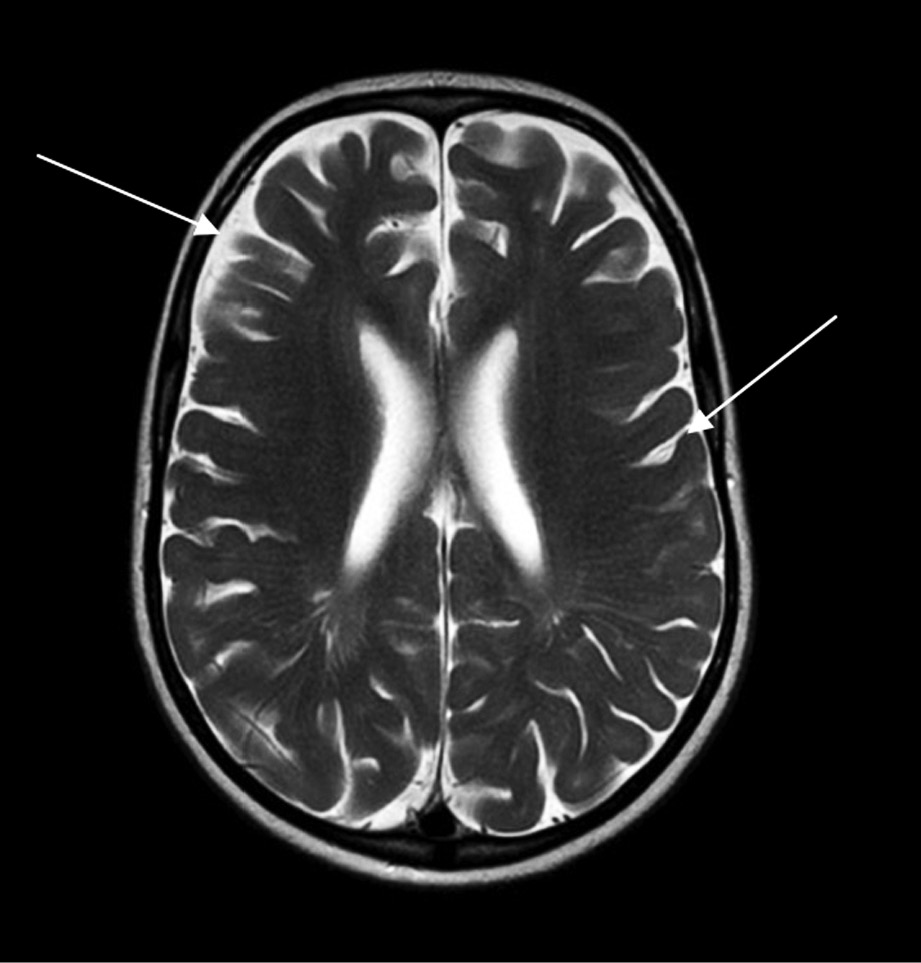

Расширенные ПВП не являются специфической находкой при МПС, т.к. встречаются и при других заболеваниях сосудистой, воспалительной, инфекционной и опухолевой природы, а также в норме. Расширения ПВП чаще всего располагаются пе-ривентрикулярно и в базальных ганглиях, однако описаны случаи локализации в стволе мозга и мозжечке [16]. Обычно диаметр ПВП варьирует от 2 до 8 мм (рис. 1, а), однако в ряде публикаций описаны и более крупные (гигантские) размеры (рис. 1, б) [8, 15, 17].

Рис. 1. МРТ головного мозга, Т2-ВИ в аксиальной плоскости: а, б — стрелками показаны множественные расширенные периваскулярные пространства; отмечается также расширение субарахноидальных пространств и борозд мозга, что свидетельствует об атрофии. Кости черепа утолщены.

Fig. 1. Head MRI, T2 WI axial plane: a, б — arrow: multiple enlarged perivascular spaces; subarachnoid space and cerebral sulci are also dilated, that indicates cerebral atrophy. Skull bones are thickened.